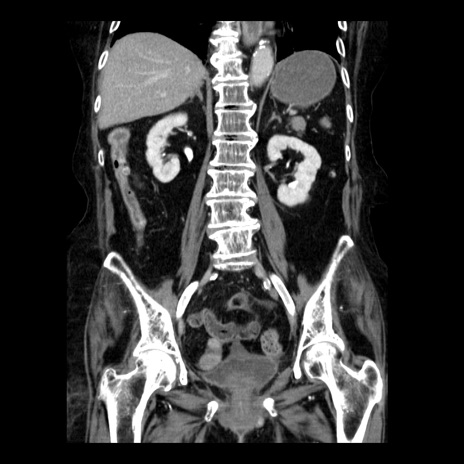

症例14(冠状断像)

【症例】 90歳代女性

【主訴】 腹痛・嘔吐

【現病歴】今朝から左側腹部痛を認めた。 経過観察していたが、嘔吐を認めたため来院。

【既往歴】 子宮癌術後

【身体所見】 意識清明、BP 127/54mmHg、P 98bpm Sp02 95%(RA)、BT 35.8°C、腹部平坦・軟腸ぜん動音聴取良好、右下腹部圧痛(+) 反跳痛なし

【データ】WBC 9800、CRP 0.46